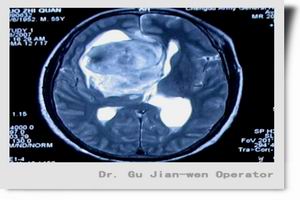

1.以往採用的氣腦造影術因併發症多、敏感性低而被淘汰,現多根據臨床表現選擇CT或MRI檢查。CT是松果體腫瘤的首選檢查,可做增強及冠狀面掃描。CT引導活檢可於病灶局部獲取組織,明確病理診斷。Fedorcsak等在1989~1996年期間進行523次CT引導定向活檢術,認為本法完全有效,對顱內腫瘤的組織學診斷、制定合適的治療方案很有必要。

2.MRI對松果體母細胞瘤診斷有獨到優點,松果體母細胞瘤起源於松果體腺,惡性程度大,具浸潤性,生長快,易轉移,病人存活期短,因而早期診斷治療十分重要。MRI顯示松果體腫瘤區域的高信號以及清晰可見腫瘤侵入第三腦室的程度。